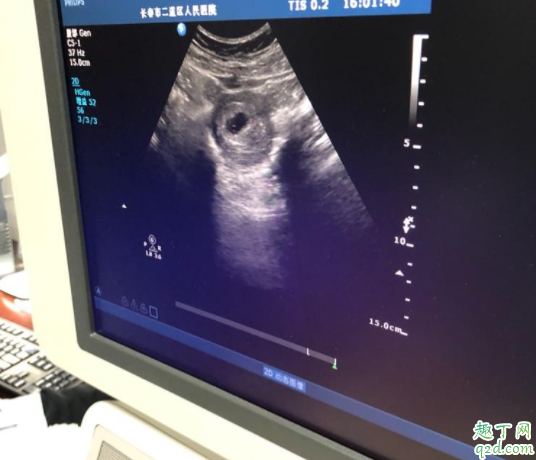

有卵黄囊没胎芽胎心多长时间可以判定胎停卵黄囊是在怀孕期间妊娠囊中最早出现的结构,大概在怀孕5周时候出现并逐渐增大,给胎芽提供营养,在12周后逐渐自行消失 。

早孕检查可以做经腹部妇科彩超和经阴道妇科彩超 。两个检查都是同样的检查原理,都是利于超声技术 。只是两个检查的检查途径不一样 。经腹部妇科超声需要憋尿,经阴道妇科彩超需要排空膀胱 。但是经阴道妇科彩超干扰更小,能够早一周看见卵黄囊、胚芽和胎心 。

有时候出现卵黄囊并不一定就会有胎心,看到胎心的时间最晚不会超过两个月 。